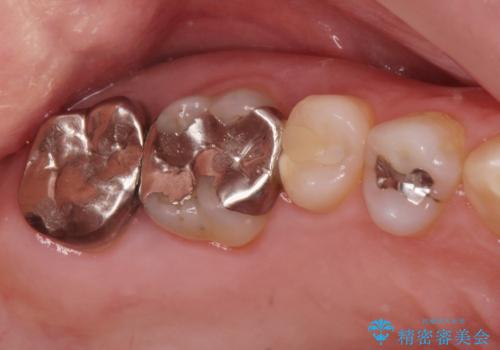

白い詰め物が入り、大変満足して頂けました。

もう一つの歯も今後治療をしていきたいそうです。